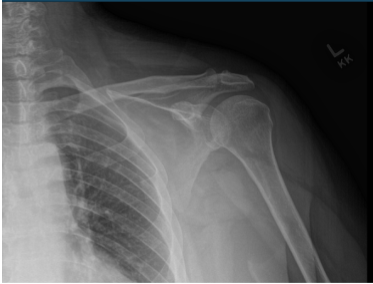

Left shoulder X Ray were presented and discussed and showed normal left shoulder radiographs. Recommended patient to undergo MRI to see the reason behind the pain. Found that there is very minimal AC joint osteoarthritis. No subacromial enthesophyte is visualized. Also noticed, mild rotator cuff tendinosis.

Left Shoulder X-ray